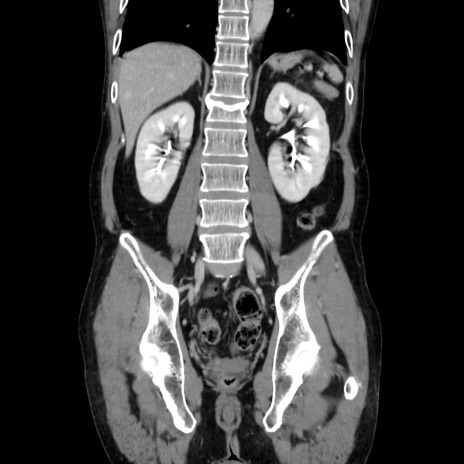

症例37(冠状断像)

【症例】40歳代 男性

【主訴】腹痛

【現病歴】4時間ほど前に電車に乗車中に臍部上より腹痛出現。徐々に増悪し起立困難となり、救急外来受診。生ものは数日食べていない。今朝お雑煮を食べた。

【身体所見】BT 36.8℃、BP 117/84mmHg、HR 91/min、SpO2 97%、苦悶様、腹部:臍上部広範囲圧痛あり、反跳痛±

【データ】WBC 8100、CRP 0.03